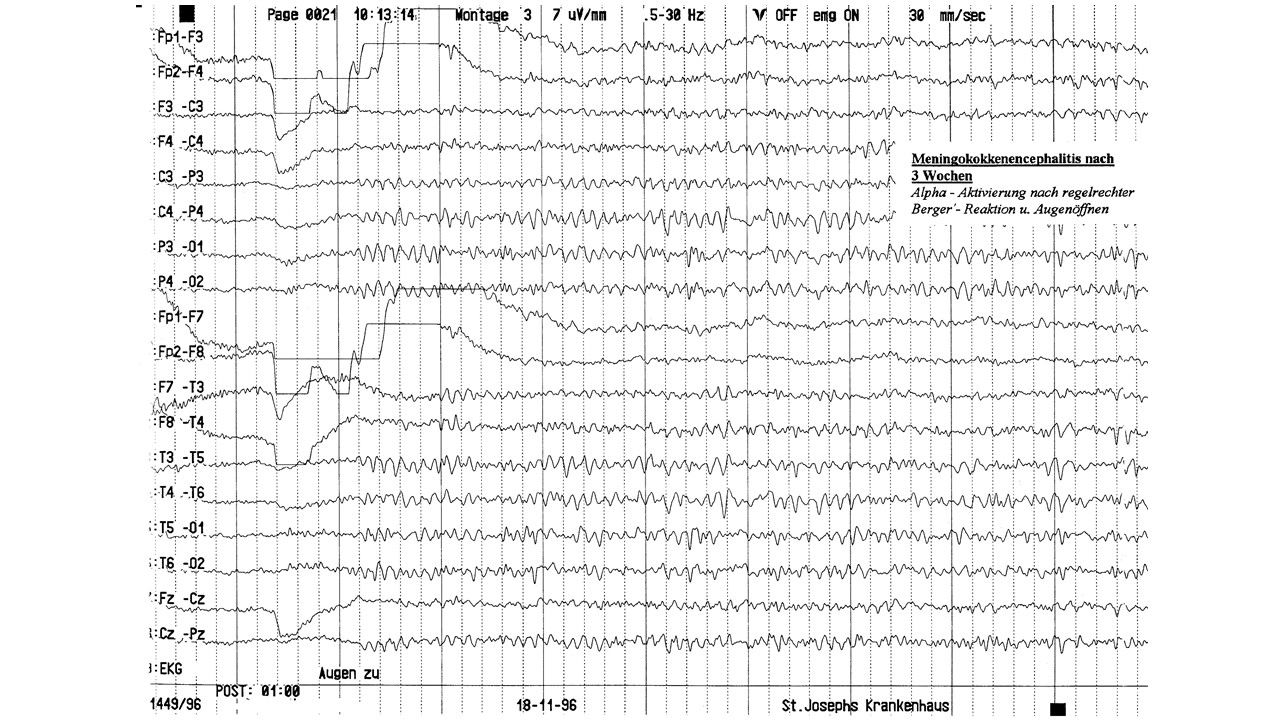

EEG-Seminar III | 15.47 zurück | weiter

folie160.jpg